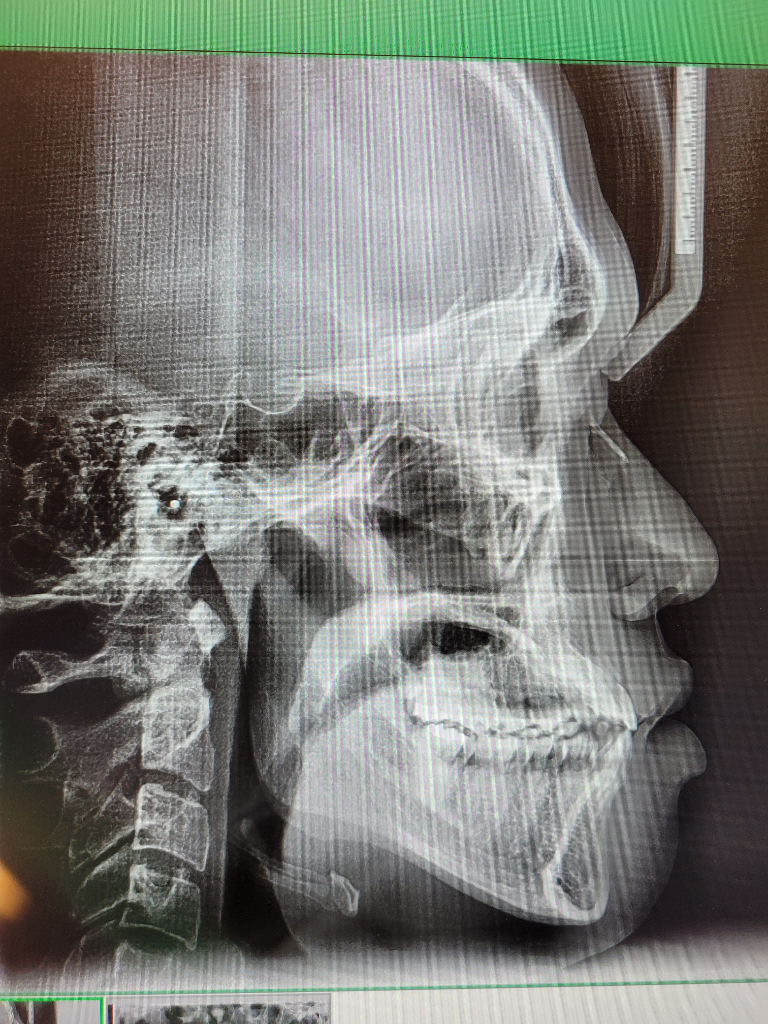

• 4번 째 사진

안녕하세요. 구강악안면외과랑 교정과 돌아봤는데 절단교합인 3급 부정교합이 있고 어금니가 잘 맞지 않는 상태라면서 돌출입 경향에 거미스마일이 있다는 진단과 함께 미세한 비대칭(3mm정도 가량)과 턱끝이 7~8mm(이마뼈 기준 턱 끝이 5mm들어간 위치를 정상으로 볼 때)가량 나왔다는 진단을 받았습니다. 그러면서 발치가 동반되는 돌출입 교정을 하면 주걱턱스러운 부분이 어느정도 개선되지만 중안면부 함몰 및 주걱턱에서 나타나는 중안모가 꺼져서 나타나는 특유의 이상한 느낌에 대한 개선과 하악이 전돌된 부분에 대한 제대로 된 개선​은 어렵다고 했습니다. 그 외의 방법으로의 주걱턱 교정은 외모 개선의 효과는 전혀 없고 교합만 맞춰진다고 했습니다. 그러면서 확실한 외모 개선(중안면부 함몰에 대한 개선과 하악이 전돌된 부분에 대한 개선)을 원한다면 상악의 발치교정으로 위턱이 들어간 상태에서 위턱을 전체적으로 전방이동하는 수술방식 혹은 양악 회전술(전문 용어로 clockwise rotation of maxilla mandibular complex, 이 술식의 경우 하악이 너무 뒤로 이동할 가능성이 높은 술식)과 더불어 이부성형술을 교합만 맞추거나 돌출입만 들어가는 정도로 생각한다면 교정을 생각해보라는 이야기를 들었습니다. 저는 확실한 외모 개선(중안면부 함몰에 대한 개선과 하악이 전돌된 부분에 대한 개선​)을 원하지만 양악수술은 구강악안면외과의 수술 중 비교적 큰 수술에 속하는 만큼 신중히 결정하고자 합니다. 우선 안모, 교합, x-ray 사진자료를 올릴 테니 수술 케이스, 보더라인, 수술 정말 필요없는 케이스 중 어디에 속하는지 대략적인 판단을 부탁드립니다. 선생님 다시 한 번 말씀드리지만 저는 확실한 외모 개선(특히 중안면부 함몰에 대한 개선​)을 원합니다!!!